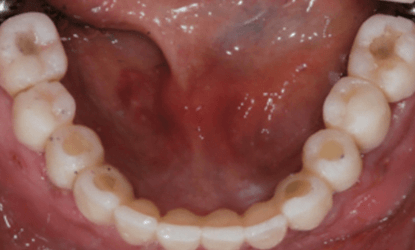

Vienmomentis priekinių dantų atstatymas laikinomis restauracijomis

Vienmomentis krūminių dantų atstatymas laikinomis restauracijomis